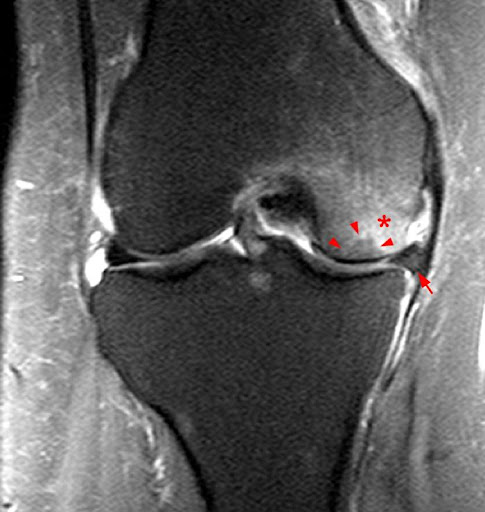

Findings Typical Of Subchondral Fracture A Coronal T1 Weighted Download Scientific Diagram